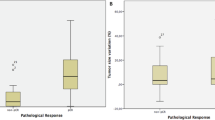

PVR ≥ 65% was observed in 17/21 patients (responders). MDpre of responders (0.99 ± 0.27 10−3 mm2/s) was significantly (p = 0.025) lower than MDpre of non-responders (1.46 ± 0.33 10−3 mm2/s). Moreover, in patients as a whole PVR significantly correlated (p = 0.01, r = −0.54) with MDpre. MDpost (1.26 ± 0.39 10−3 mm2/s) of responders was significantly(p = 0.024) higher than MDpre (0.99 ± 0.27 mm2 10−3 mm2/s), whereas non-responders MDpost (1.00 ± 0.14 10−3 mm2/s)did not increase compared with MDpre (1.46 ± 0.33 10−3 mm2/s).

MDpre of responders (0.99 ± 0.27 10−3 mm2/s) was significantly (p = 0.025) lower than MDpre of non-responders (1.46 ± 0.33 10−3 mm2/s) (Figs. 1, 2, 3). Moreover, in the group of patients as a whole (responders and non-responders) PVR significantly correlated (p = 0.01, r = −0.54) with MDpre (Fig. 4). In responders (Fig. 5) MDpost (1.26 ± 0.39 10−3 mm2/s) was significantly (p = 0.024) higher than MDpre (0.99 ± 0.27 10−3 mm2/s) whereas in the small group of non-responders (Fig. 6) MDpost (1.00 ± 0.14 10−3 mm2/s) decreased with respect to MDpre (1.46 ± 0.33 10−3 mm2/s) but not significantly (p > 0.05).